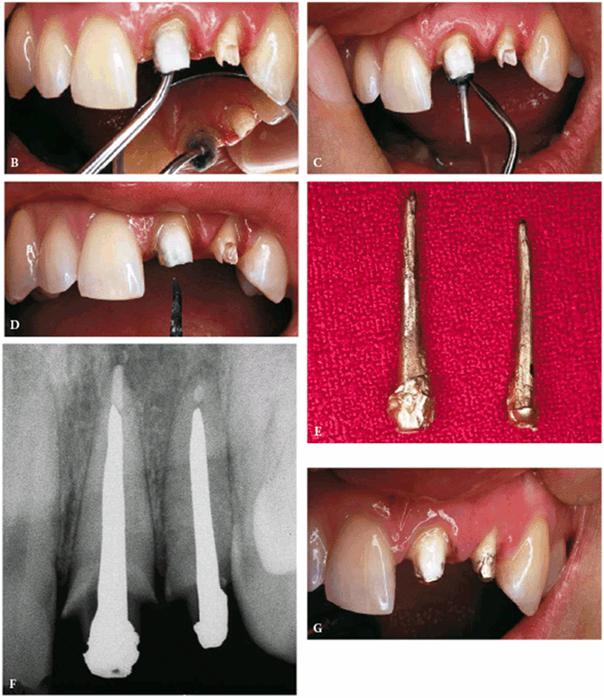

on both teeth (Figur 323s1823d es 18-7A

Figur 323s1823d e 18-7A and B: Although this 12-year-old girl was referred to an oral surgeon for a postaccident extraction of both fractured central incisors, he wisely referred the patient to an endodontist in an attempt to save the teeth.

TREATMENT: Because saving teeth was a step-by-step procedure involving

endodontic treatment, periodontal surgery, and reconstructive techniques, the

treatment plan could be changed if one of the suggested treatments failed.

Endodontic therapy had already been completed on both central incisors. These

surgical procedures were performed next: removal of the tooth fragments that

were fractured vertically, labial and lingual gingivectomy and gingivoplasty,

palatal ostectomy, and labial frenectomy (Figur 323s1823d e 18-7C). Approximately 5 mm of palatal

plate was removed to expose new margins on the fractured teeth (Figur 323s1823d e 18-7D). After the tissue healed, gold

posts were constructed and cemented on the two maxillary incisors (Figur 323s1823d es 18-7E to

H). Final

preparations were made, and impressions for aluminous porcelain crowns were

made. The two crowns were seated (Figur 323s1823d es 18-7I

and J Figur 323s1823d e 18-7K is a radiograph of the teeth at the

end of treatment.

Figur 323s1823d e 18-7C and D: Following endodontic therapy and removal of the fractured tooth fragments, periodontal surgery to lengthen the exposed crowns was performed.

Figur 323s1823d e 18-7E to H: Next, two posts and cores were constructed for the endodontically treated teeth.

Figur 323s1823d e 18-7I and J: Two aluminous porcelain crowns were constructed and inserted on the central incisors.

Figur 323s1823d e 18-7K: Post-treatment radiograph of the two fractured and restored central incisors.